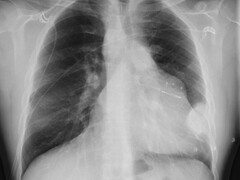

Beeldquiz

Stel je diagnose op basis van een foto. De wekelijkse beeldquiz van het NTVG is een leuke manier om je kennis snel te testen en te vergelijken met anderen.